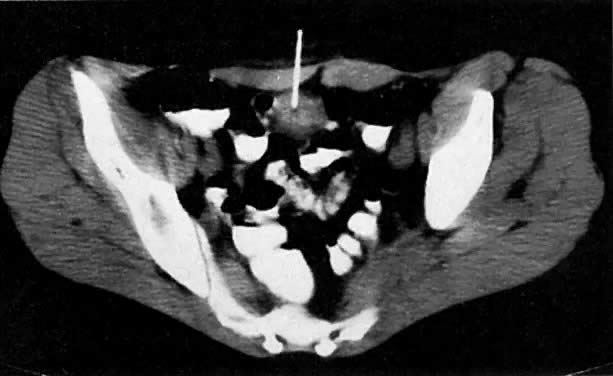

Endometrial carcinoma is demonstrated as a central area of hypodensity relative to the enhanced normal myometrium on postcontrast CT (Fig. 23).56 More often, CT shows diffuse uterine enlargement. It is often impossible to differentiate endometrial carcinoma from benign causes of uterine enlargement (e.g., fibroids) by CT.

Fig. 23. A 61-year-old woman with endometrial cancer. Note enlargement of the uterus ( u) with a central area of hypodensity and the surrounding ascites ( a ).